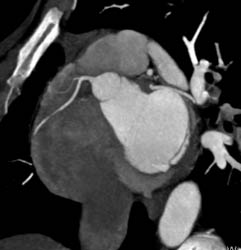

LAD in 3D